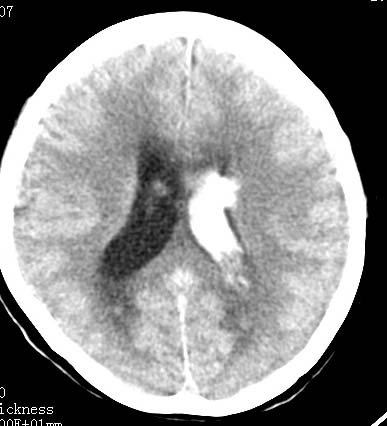

标题: CT9945:男性 病人 请大家看看出血的部位究竟在哪里? [打印本页]

标题: CT9945:男性 病人 请大家看看出血的部位究竟在哪里?

男性 病人 请大家看看出血的部位究竟在哪里?

是不是脑室系统出血啊! 伴轻度脑积水! 请老师指教!!

脑室系统出血,并脑积水.

我觉得是左侧侧脑室体旁出血,破入脑室系统.理由:除了左侧脑室体部外缘不规则之外,还有就是左侧脑室里面出血量较右侧多!

应该是左侧侧脑室内的出血导致其他脑室内的积血。

应该是尾状核出血破入侧脑室.

1、原发脑室出血,出血部位应该是左侧侧脑室;

2、左侧基底节区腔隙性脑梗塞;

(不考虑脑积水,脑室急性出血期脑室系统会轻度扩张)

脑室系统出血,第三脑室,侧脑室都有

左侧尾状核体部出血破入脑室系统.

最重要的是要讲明以脑室内积血为主,脑积水